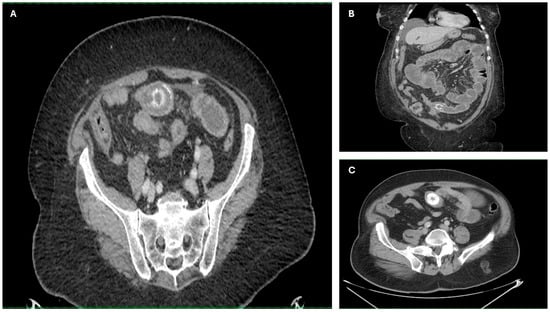

Imaging findings were consistent with biliary ileus, characterized by the presence of ectopic gallstones within the gastrointestinal tract. As shown in Figure 3A–C, axial and coronal CT images demonstrated radiopaque enteric gallstones. Figure 4 highlights a gallstone associated with a cholecystoduodenal fistula. Further axial and coronal sections (Figure 5A–C) show additional enteric gallstones, including one in the rectal ampulla.

Figure 3. Radiological features of enteric gallstones in biliary ileus. (A) Axial CT section demonstrating a highly radiopaque enteric gallstone located within the intestinal lumen, consistent with biliary ileus. (B,C) Coronal and axial reconstructed CT images further illustrating the presence of an enteric gallstone causing intestinal obstruction—features characteristic of biliary ileus. Acquisition with 5 mm slice thickness and 3 mm reconstruction. Images have been cropped and zoomed for optimal visualization while maintaining the original scale; a 10 mm scale bar is included in each panel.